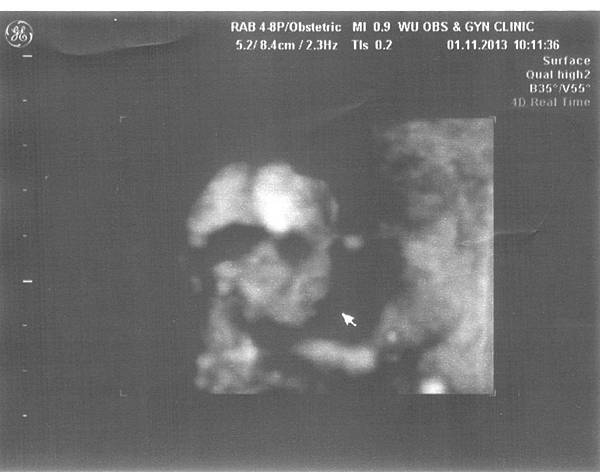

14w0d-116w6d-115w2d-115w2d-216w6d-1